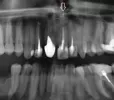

Передний зуб (верхняя челюсть) был восстановлен, простоял лет 7 где-то. Сейчас треснул и шатается свой только корень, остальное вылеплено из искусственного материала, за это время была киста и делали резекцию корня. Подскажите, пожалуйста, какой вариант наиболее приемлем в такой ситуации?

Можно ли в этот корень установить вкладку и потом сверху металлокерамику? Или может быть в соседний (он тоже восстановлен) тоже сделать вкладку, чтобы сразу две коронки одеть, с расчетом, что если коронки будут скреплены между собой, держаться будет лучше и нагрузка на корень с резекцией верхушки будет меньше?

Все верно, вы абсолютно правы, необходимо изготовить одновременно культевые вкладки и затем коронки. Запишитесь к нам на прием, я вас посмотрю и расскажу как необходимо сделать, чтобы избежать чрезмерной нагрузки на 21 зуб.